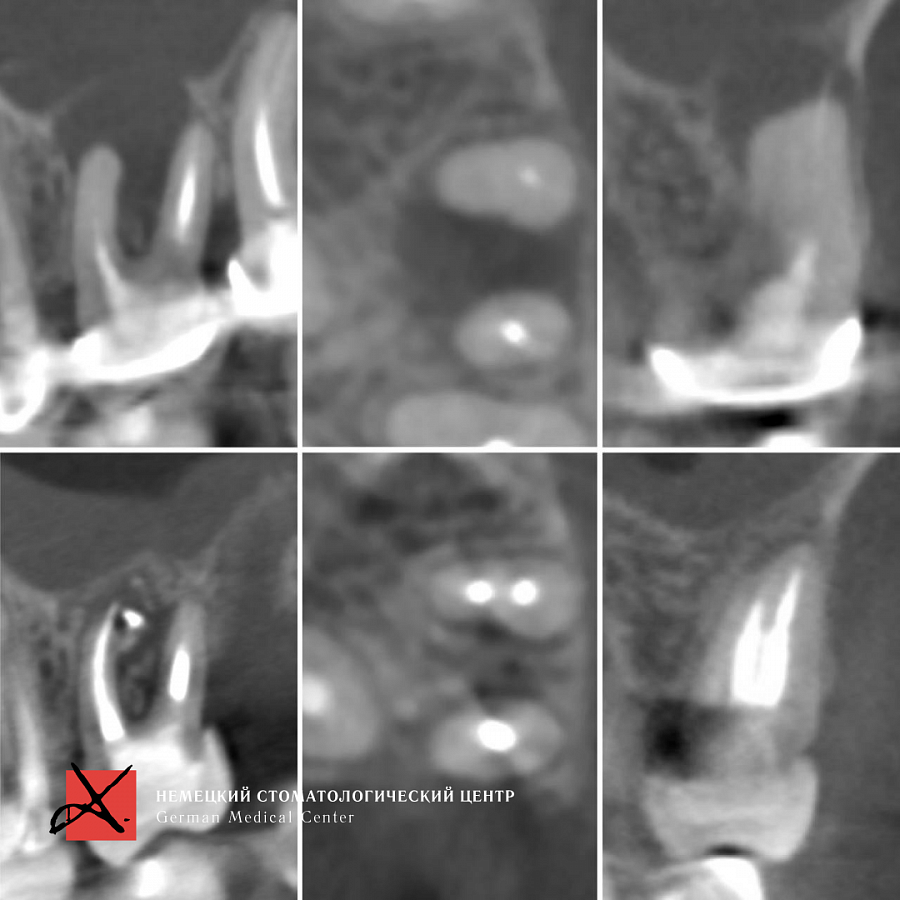

Лечение каналов под микроскопом